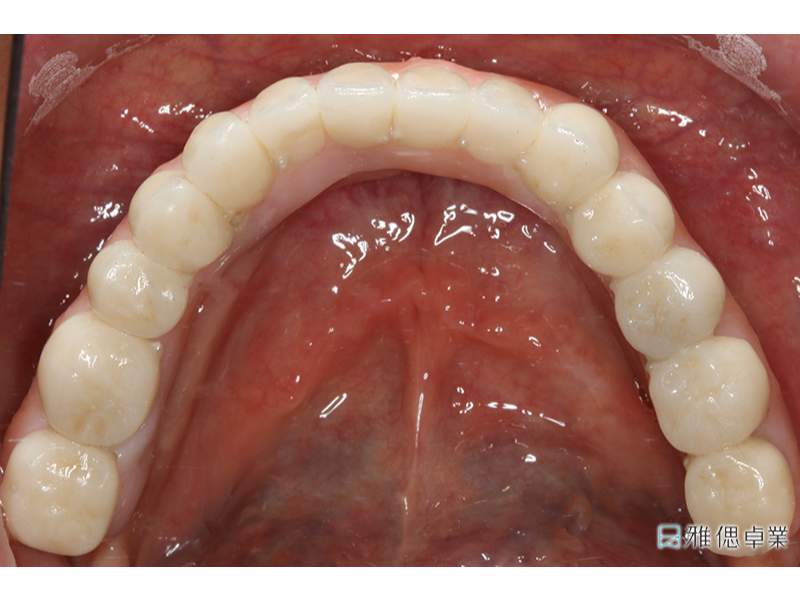

All on 6正式假牙(上顎)

假牙模型上顎